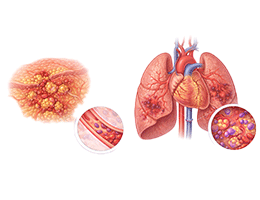

심근경색 (Myocardial Infarction)

협심증 (Angina Pectoris)

부정맥 (Arrhythmia)

심근병증 (Cardiomyopathy)

심장판막질환 (Valvular Heart Disease)

심부전 (Heart Failure)

비대성심근병증 (Hypertrophic Cardiomyopathy)

확장성심근병증 (Dilated Cardiomyopathy)

울혈성심부전 (Congestive Heart Failure)

심근염 (Myocarditis)

심막염 (Pericarditis)

심내막염 (Endocarditis)

심방세동 (Atrial Fibrillation)

심실빈맥 (Ventricular Tachycardia)

심실세동 (Ventricular Fibrillation)

폐동맥고혈압 (Pulmonary Hypertension)